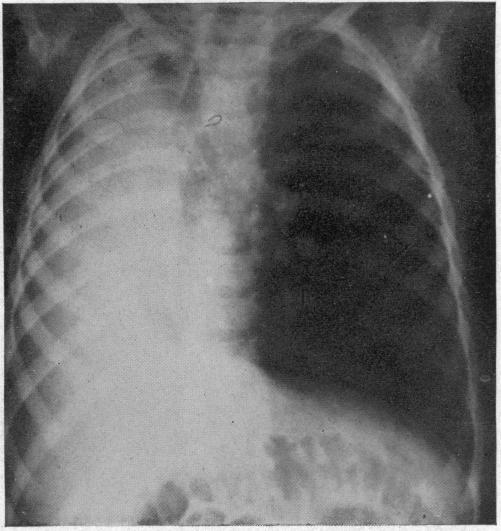

ACUTE MASSIVE COLLAPSE OF THE LUNGS: A DISCUSSION OF ITS MECHANISM AND OF ITS RELATION TO FOREIGN BODIES IN THE BRONCHI AND POST-OPERATIVE COMPLICATIONS.

摘要